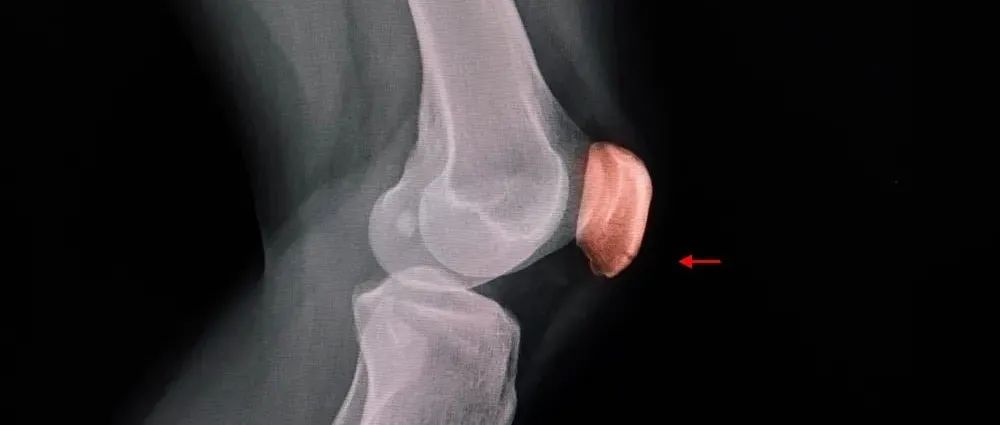

髌骨骨折的治疗方案与并发症防治方法

髌骨骨折只占全身骨折的 1%,治疗方式的选择和并发症的防治尤其要注意,急诊来了髌骨骨折患者,你怎么处理?解剖髌骨是人体最大的籽骨,位于膝关节伸膝装置内。解剖特点包括近端宽大的基底和关节外的远侧尖端,前面位于关节外,后面为关节面。图源:站酷海洛股直肌和股中间肌止于髌骨基底部,股内侧肌和股外侧肌止于髌骨的两侧。髌腱起于髌骨尖端,止于胫骨结节。髌骨骨折的诊断髌骨骨折约占所有骨折的 1%,主要由直接暴力造成,如跌倒时跪地或膝关节屈曲时受到打击。...

髌骨骨折的治疗方案及并发症防治